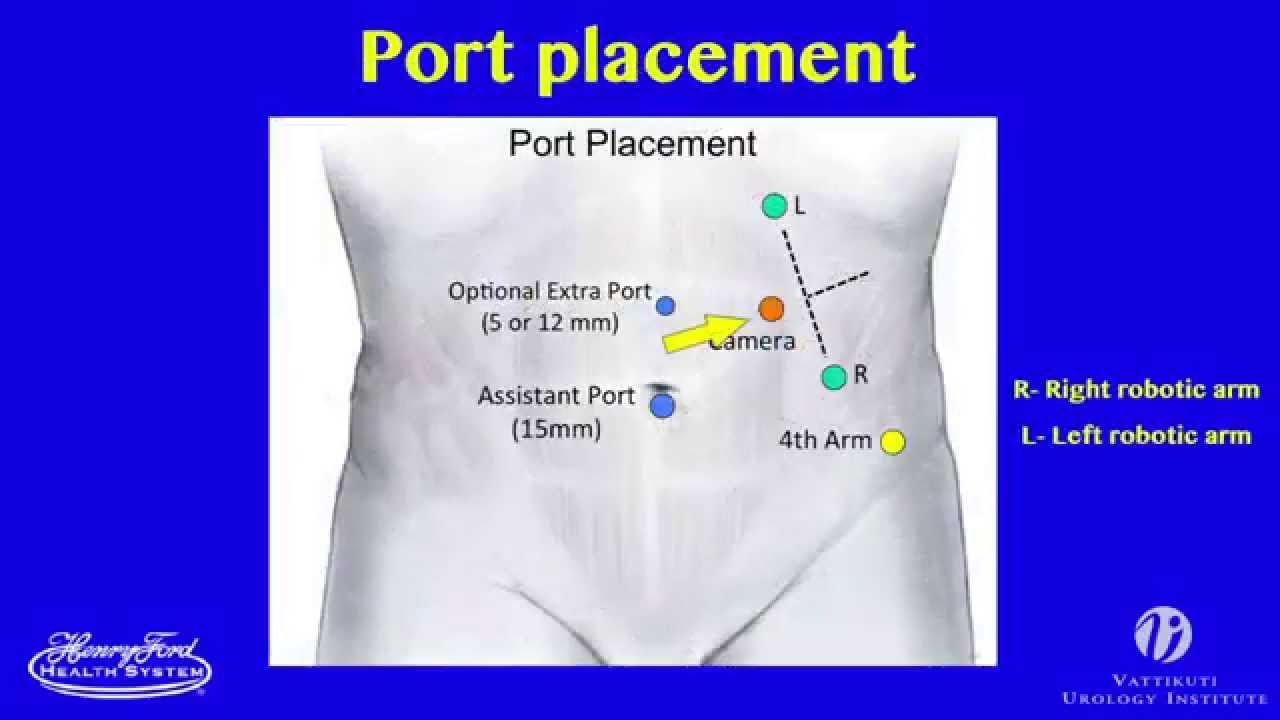

Port Placements by Indian (Manipal) Modification for da Vinci X Surgical System